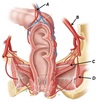

Name structures A to E

A - Rectus abdominus

B - External oblique

C - Internal oblique

D - Transversus abdominus

E - Parietal peritoneum

Name structures A to E

A - External oblique

B - Internal oblique

C - Transversus abdominus

D - Parietal pleura

E - Rectus abdominus